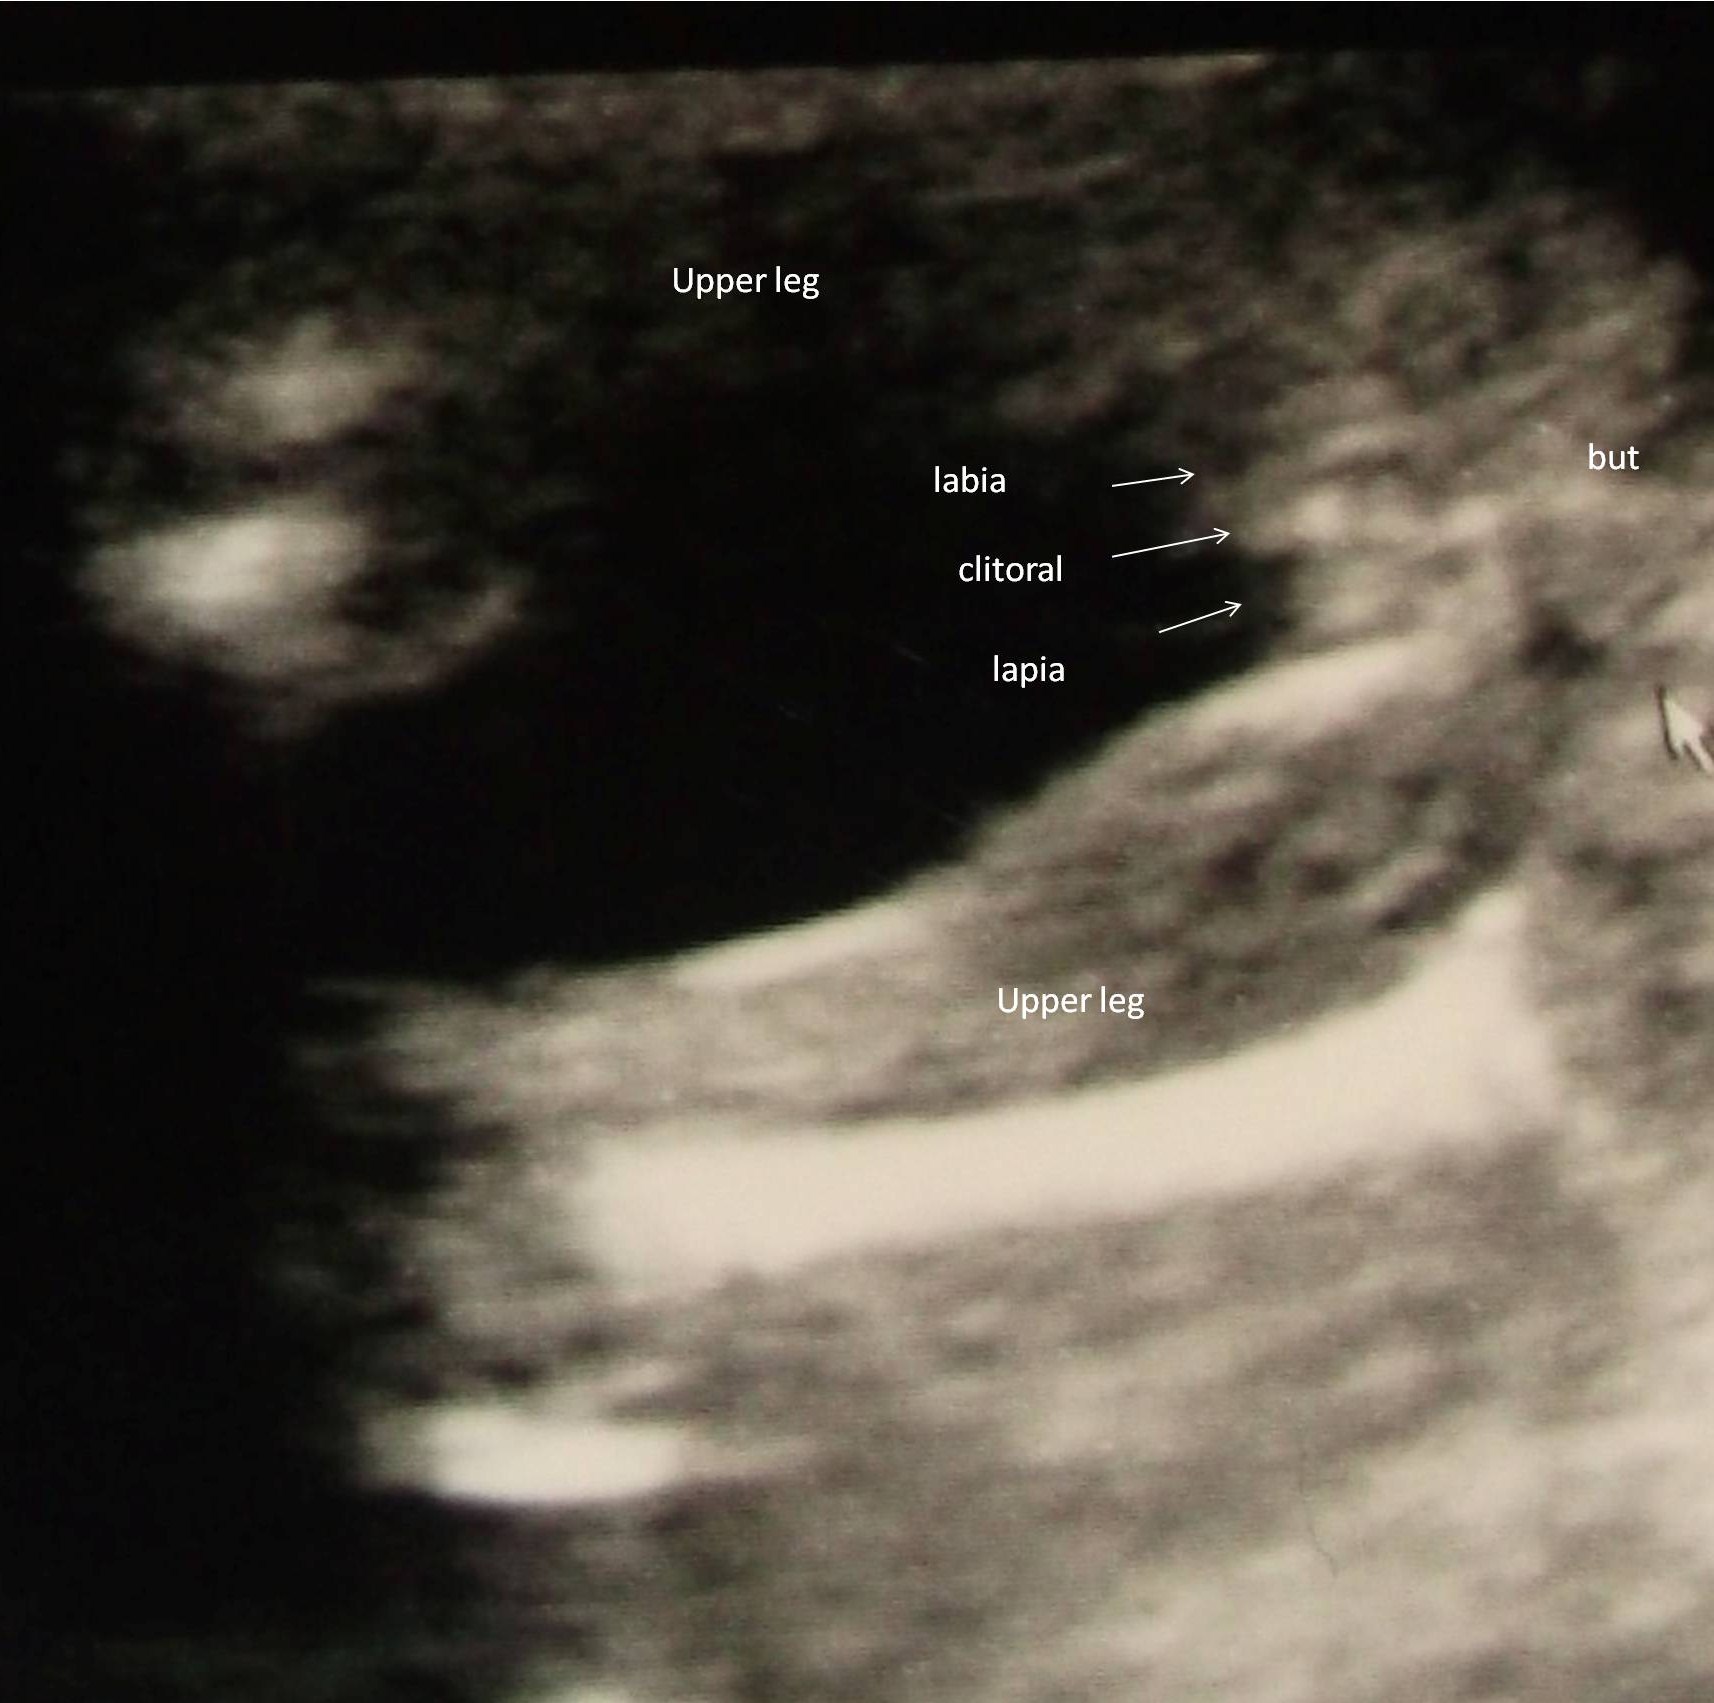

I saw the Girl parts on the Monitor it was so touching , but to print out a picture was forgotten again :-D so he started again and made this picture witch I don’t find as good as that what I saw on the monitor! Anyway it seems so to be a Girl :-D The doctor said that some boys have “displaced elevation testis” and that this is the only possibility if it’s not a Boy!

So ladies can I tell my family on eastern that we are having a Girl and should I start buying Piiink ???? :-D

Attachment 9987